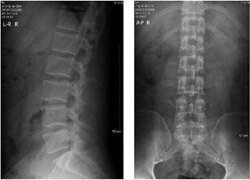

张缪佳在解释“强直性”一词时介绍:“人体髂骨和骶骨间有个关节称为骶髂关节,该关节是强直性脊柱炎最早发生症状的部位,所以早期主要症状是下腰部疼痛。随着病情进展,从骶髂关节往上蔓延,逐步发展到腰椎、颈椎、胸椎椎角炎。椎角炎症基础上的骨质增生,导致骨赘形成,脊柱逐渐变得僵硬,患者的脊柱活动度缓慢下降。正因为有僵背这样的表现,所以称为强直性脊柱炎。”

有很多强直性脊柱炎患者提出,脊柱会随着病情发展变成像竹节一样,最后导致骨头融合在一起。这是为什么呢?张缪佳说:“人的脊柱,是由节节椎体连接在一起组成,分为七节颈椎、十二节胸椎和五节腰椎,它们有不同的身体曲度,既起到了支撑,也让我们变得非常灵活。”

“强直性脊柱炎的早期患者,可在脊柱椎体最边缘的地方出现炎症破坏,连接脊柱间的韧带炎症后出现骨化形成骨赘。上下的骨赘会慢慢生长,直至连接起来变成骨化的脊柱。当椎体连接在一起后,就像竹子中间的节,一节一节相连看上去非常像竹节,从医学角度称为竹级样改变,这是强直性脊柱炎的晚期表现,此时患者脊柱活动会受到很大限制。”张缪佳表示。